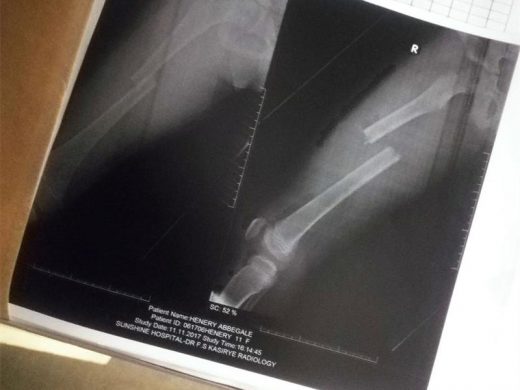

Southcrest residents Martin and Abbegale Henery (a Laerskool President Steyn learner) were both injured but Abbegale will need at least eight weeks to recover from her clean-broken thighbone, punctured leg and loss of skin on her lower right leg – if her recovery goes according to plan. Martin was lucky to leave the accident with only a cracked right hand and a few bruises and cuts.

CLEAN BREAK: Abbegale’s x-ray reveals a terrifying injury to her right thighbone.